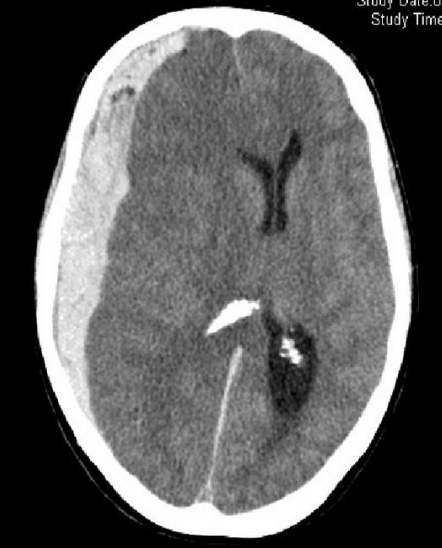

Intracerebral hemorrhage

Infarction appear hypodense on CT without contrast

Sign? Hyperdense sign in stroke; LT Middle cerebral artery hyperintense

Y

Dense basilar artery and middle cerebral arteries on CT

Thrombus in vessel is hyperdense relative to flowing blood